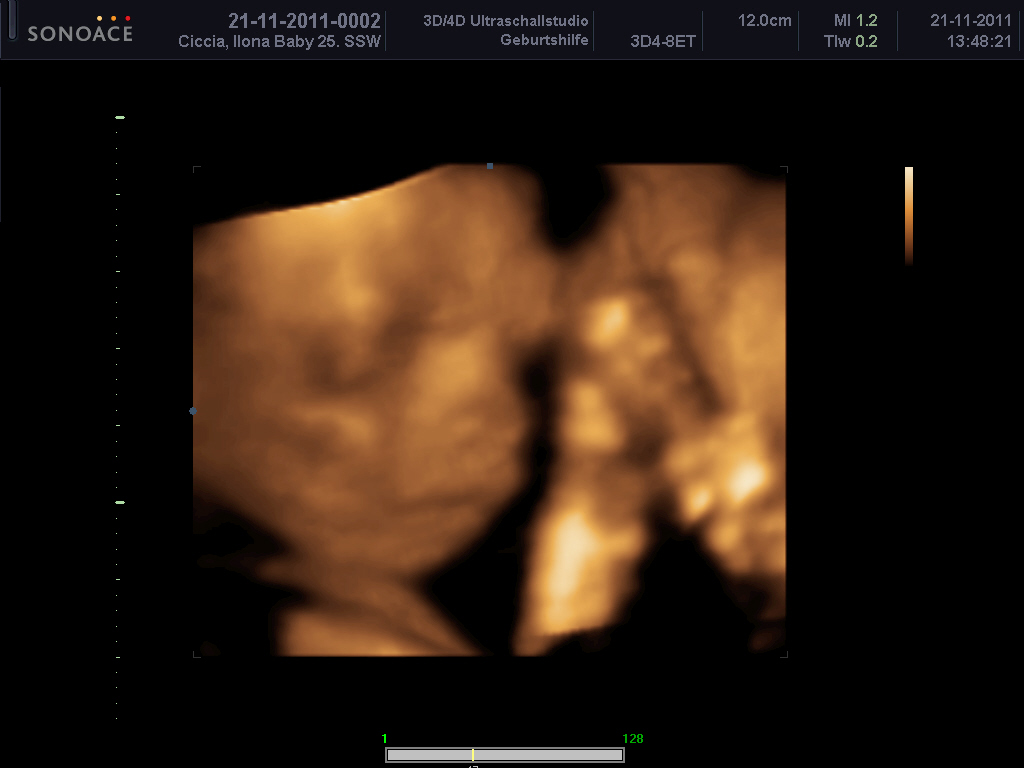

wieder zuhause =) mit 200 fotos und einer 1-stündigen dvd :räusper:

Weil sich die kleine immer nur mit hand vor dem gesicht gezeigt hat, mussten wir über ne stunde schallen bis sie sich mal bequemt hat sich zu zeigen *g*

Ich hänge euch mal ein Bild mit an.

ERINNERUNG21112011_0155.JPG

ERINNERUNG21112011_0180.JPG

ilo: sind das schöne Bilder, so 3 D find ich eh viel besser als die normalen. Rosa ist auch nicht so meins, deswegen hab ich da nie viel von gekauft. Aber pass mal auf, wenn Madame dann selber aussuchen will was sie anzieht. Pferde müssen drauf sein oder Prinzessinen, was soll man machen? :?: